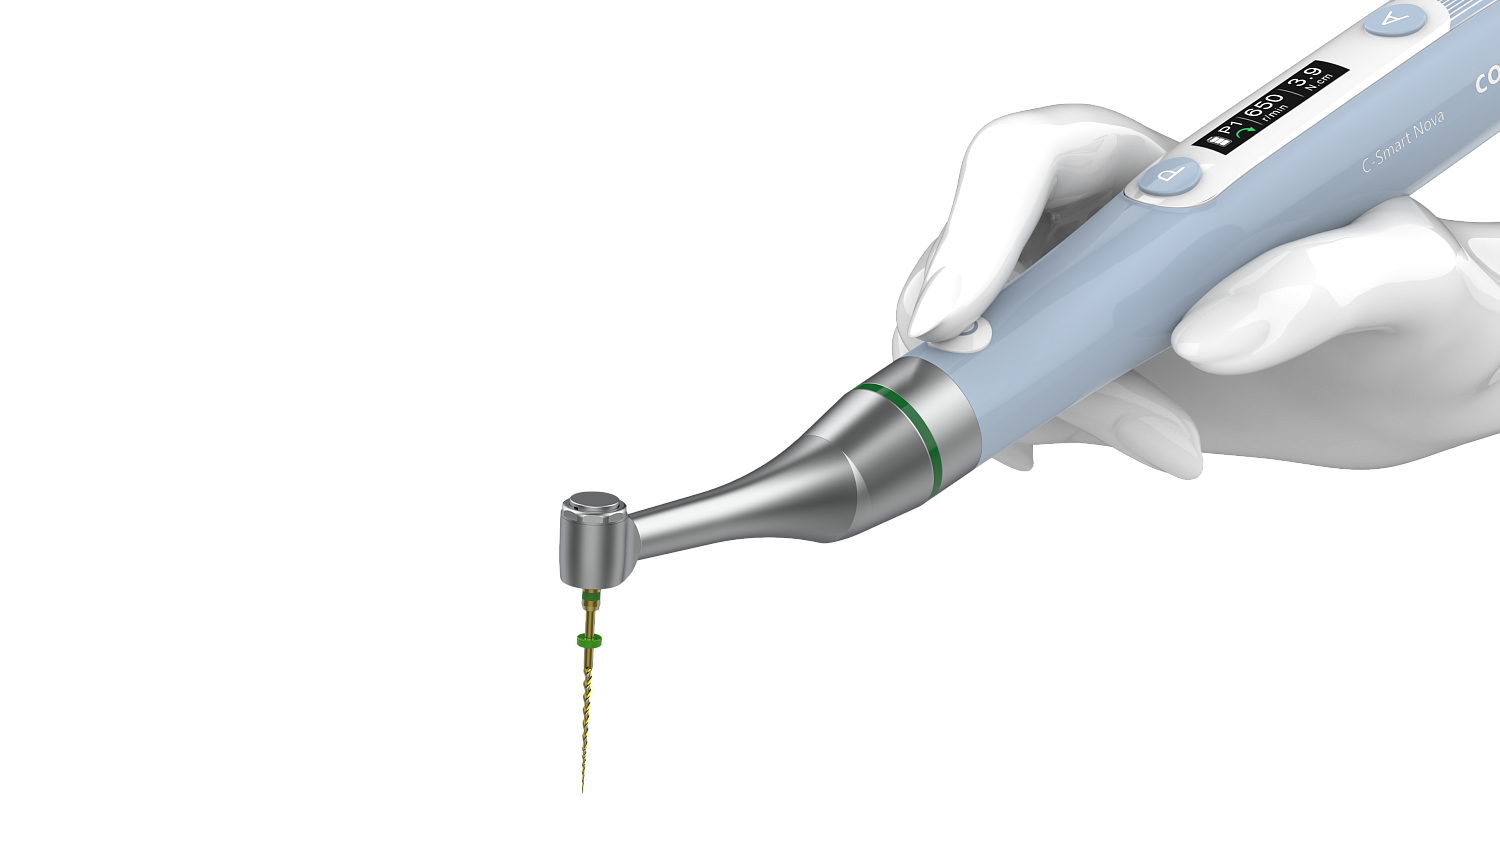

Диапазон регулировки крутящего момента - 0,6 - 3,9 Н/см. Диапазон регулировки скорости - 100 - 1000 об/мин. 5 встроенных программ: - Р1 - Р3 - режим непрерывного вращения. - P4 - режим возвратно-поступательного вращения. - P5 - режим возвратно-поступательного вращения OGP. Эргономичное и удобное использование: легкий вес (104 г), малый шум. Миниатюрная головка 8 х 10,2 мм |

| Препарирование корневого канала |